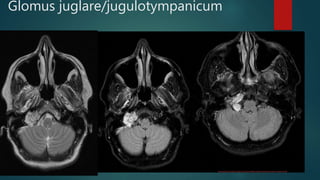

Glomus juglare/jugulotympanicum